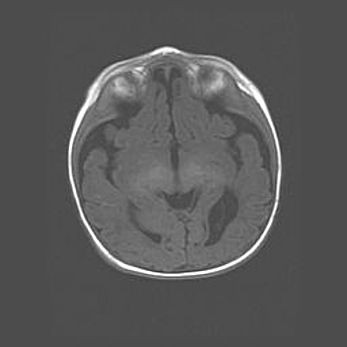

Наружная гидроцефалия с возможной атрофией височных областей.

Возраст: 28 дней

Вес: 3670 г

Пол: мужской

Окружность головы: 38 см

Срок гестации: 40 недель

Гидроцефалия головного мозга у новорожденных – это заболевание, которое характеризуется скоплением избыточного количества спинномозговой жидкости в желудочковой системе головного мозга в результате затруднения её перемещения от места выработки к месту поглощения в кровеносную систему или вследствие нарушения абсорбции. При открытой наружной форме гидроцефалии у новорожденных расширяются и переполняются субарахноидные пространства.

При нормотензивных  формах,  которые,  как  правило,  являются  следствием  перенесенных ишемических  повреждений  паренхимы  мозга,  возможно  сочетание микроцефалии  с нормотензивной гидроцефалией. В основе данных изменений лежит атрофия больших полушарий с преимущественной  локализацией  в  лобно-височных  областях.